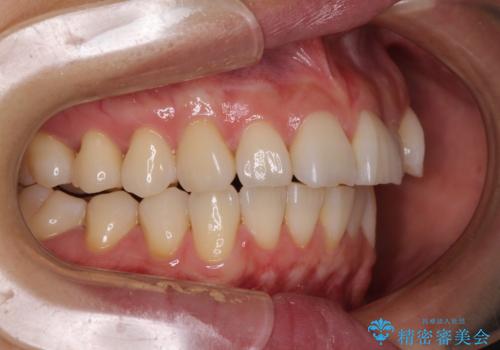

- 奥歯の咬み合わせと、上下前歯の隙間を気にして来院された患者様です。

上顎の歯列全体が、下顎歯列に対して前方に位置しており、その影響で上顎前歯がやや前方に突出している状態でした。

横顔の印象から、抜歯をして積極的に口元を引っ込める必要はなかったため、アンカースクリューを用いて上顎歯列全体を後方に移動させることとしました。

奥歯の咬み合わせは理想的な状態に改善され、その結果として上下歯列もバランスの良い位置に収めることができました。

若干ではあるものの上顎前歯を内側に移動させることができ、以前よりも口が閉じやすいと感じるようになりました。